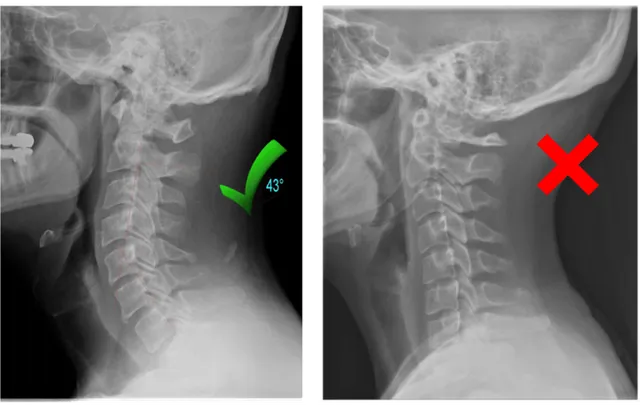

2. Your Neck Has Lost Its Natural Curve

Years of looking down at phones, working at desks, and poor sleeping posture can flatten the natural curve of your neck.

This leads to collapsed vertebrae, pinched nerves, and chronic pain that no massage or pillow can fix.